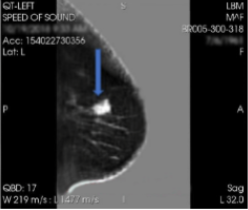

Quantitative Transmission (QT) Imaging

So, this is new and fun. My nurse refers to this type of breast imaging as ‘boob in a bowl’. It really is. You lay on your stomach on a fancy table and your boob goes in a bowl of nice warm water and it just sits there. QT imaging is a type of ultrasound imaging, specifically utilizing “quantitative transmission ultrasound” technology to create true 3D images of the breast. It’s safe. It’s fast. It’s painless.

Because QT imaging uses ultrasound, it does not involve ionizing radiation. The high image resolution allows for visualization of even significantly dense breast tissue. These images have incredibly high resolution and can be repeated in close sequence to follow suspicious lesions over time, potentially reducing the need for additional imaging or biopsy in some patients. By providing detailed tissue information, QT imaging may enable earlier detection of suspicious lesions, potentially leading to earlier diagnosis and treatment of breast cancer.

However, however, however, like conventional ultrasound, QT imaging is not recognized as a standalone screening tool for breast cancer. There are no scanners nearby if you happen to be in my neck of the woods. And the equipment is on the spendy side – trust me I’ve looked into it. If anyone wants to crowd fund this, please hit me up in the comments. We’ll name the breast cancer center after you:)

QT uses sound waves transmitted through a water bath which provides a true 3D image of the breast. It’s safe. It’s fast.